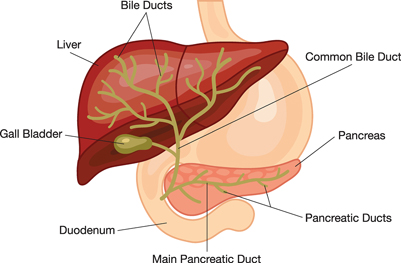

by Kimberly Allen, RN Primary biliary cirrhosis is a chronic condition in which the bile ducts in...